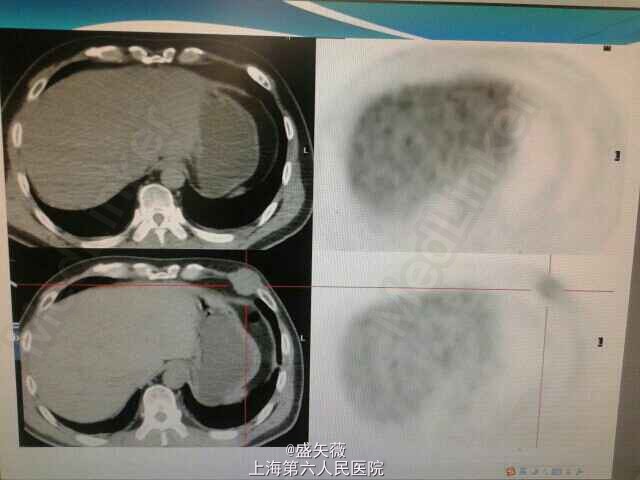

体检胸部CT示左侧胸膜占位。

术后随访pet:广泛转移。